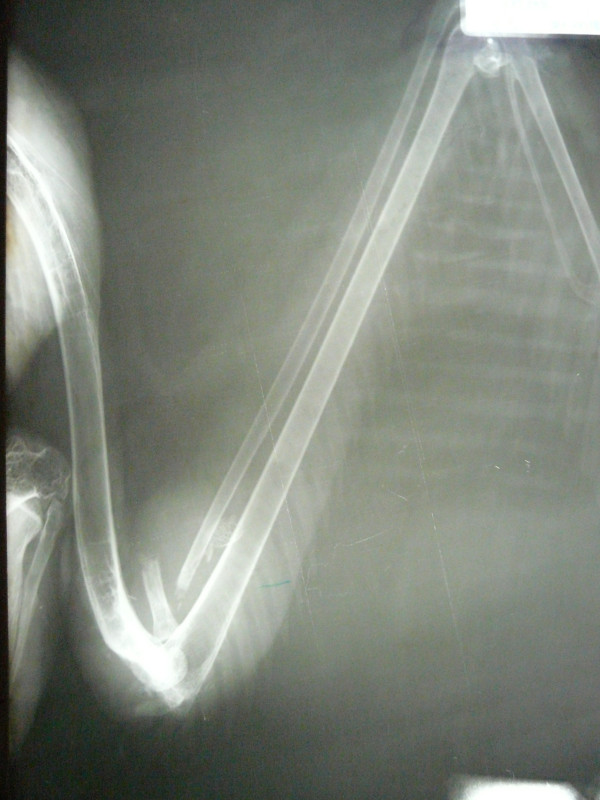

Por otro lado, y con mucha peor suerte, el domingo 11 de Noviembre ingresaba el ejemplar de buitre negro con signos de traumatismo, débil y deprimido, apenas se ponía en pie y tenía un ala descolgada. Se diagnosticó una fractura de radio y luxación de codo, pero su estado era tan grave que se decidió esperar 24 horas para realizar la radiografía, en la que encontramos más de 25 perdigones distribuidos por todo el lateral derecho del cuerpo y algunos dentro de la cavidad corporal y en la cabeza, confirmando además nuestros peores temores: había fractura también de húmero a nivel del codo, lo que hacía que este ejemplar de buitre negro ya apuntara como irrecuperable para el resto de sus días. El desplazamiento de los fragmentos en la zona de la articulación del codo había provocado una inflamación gravísima en la zona y destrucción de los tejidos blandos (musculatura, cápsula articular, ligamentos) y empezaba a haber pérdida de sensibilidad y fallo vascular en la parte más distal del ala.

Decidimos intervenir quirúrgicamente el pasado miércoles viendo que la inflamación del codo iba cada vez a peor y que el animal estaba dejando de comer por el dolor y las molestias. Durante la cirugía pudimos comprobar que la vena cubital había sido dañada por los fragmentos de hueso y se había producido una acumulación severa de líquido, además de inicio de necrosis de algunos músculos y tendones.

La tremenda decisión que tuvimos que tomar fue la de amputar el ala a nivel del húmero distal (para conservar la mayor longitud de ala posible). Tras 4 largas horas de cirugía, el animal despertó y hoy está comiendo bien de nuevo aunque aún adaptándose a la pérdida de un ala casi completa. Su futuro será pasar a formar parte del núcleo reproductor de GREFA, sabiendo que nunca más podrá volver a volar y pasar el resto de su vida en las mejores condiciones posibles pero en cautividad.